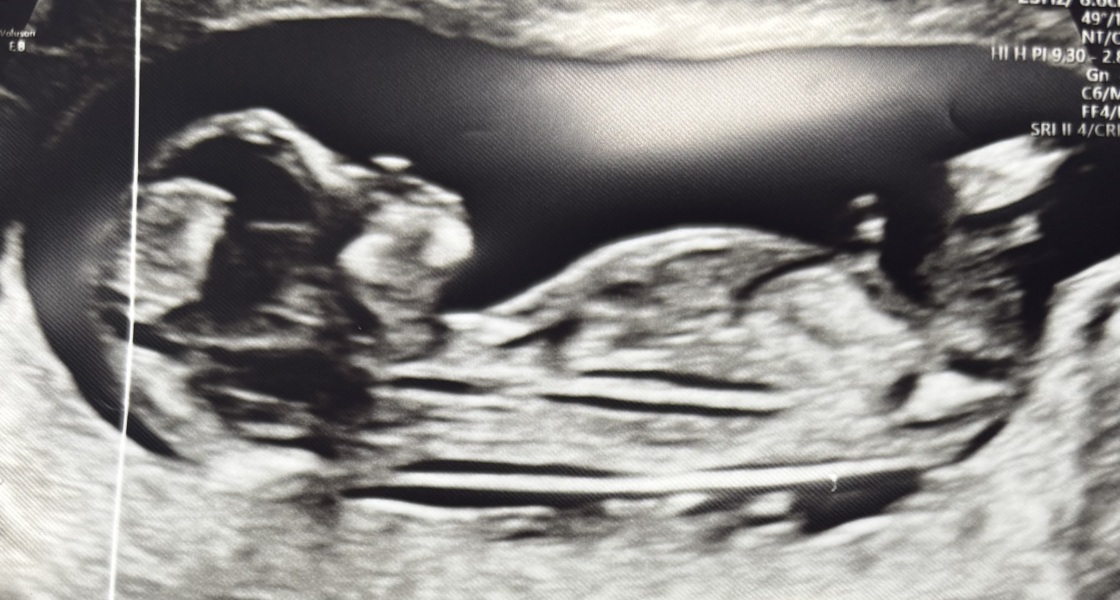

Take your guesses on the nub theory

boy or girl ?

12 weeks 2 days